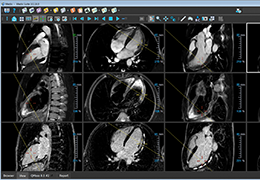

View X-Ray CT & MRI Scans Fast and Easily

Designed for surgeons, Pro Surgical 3D makes it easy to view patient scans quickly. Pro Surgical 3D facilitates the optimal 3D treatment and assessment workflows based on X-ray CT and MRI scans – and best of all, it’s FREE!

Traditional multi-planar slicing

Designed mainly for CT and MR DICOM modalities.

Multi-planar slicing.

Oblique slicing.